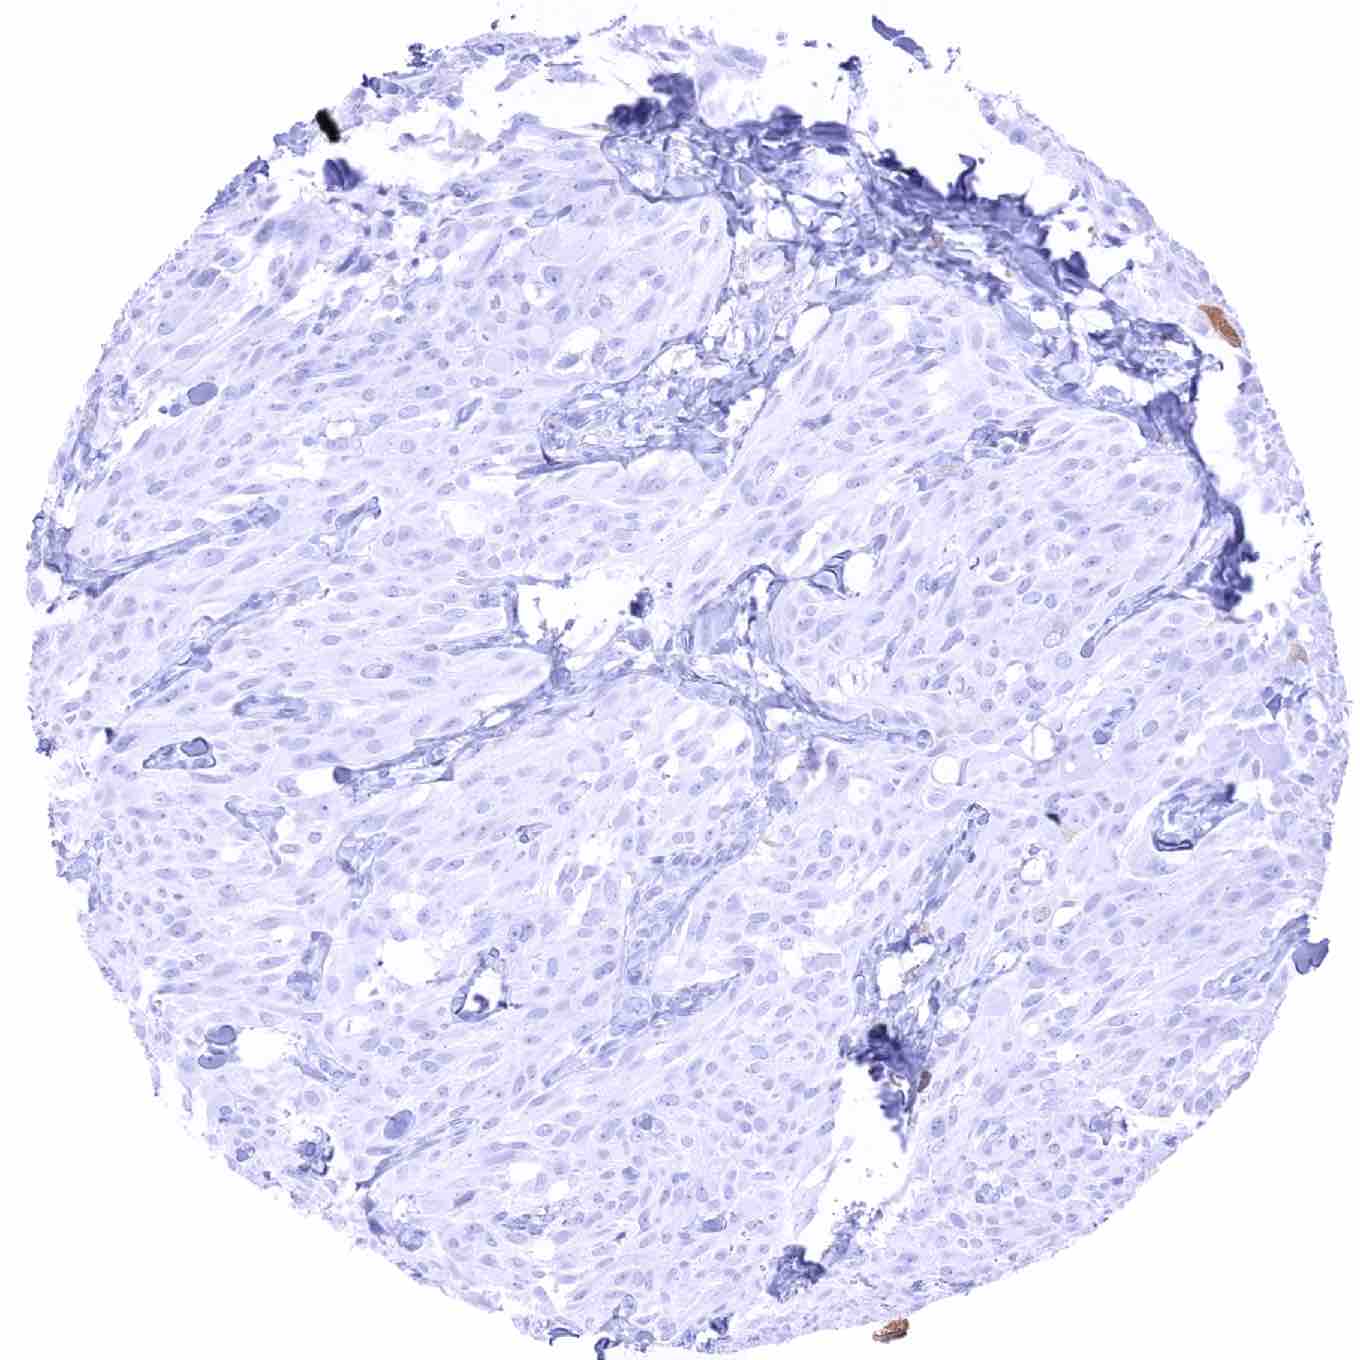

Urinary bladder – TYMS negative muscle-invasive urothelial carcinoma